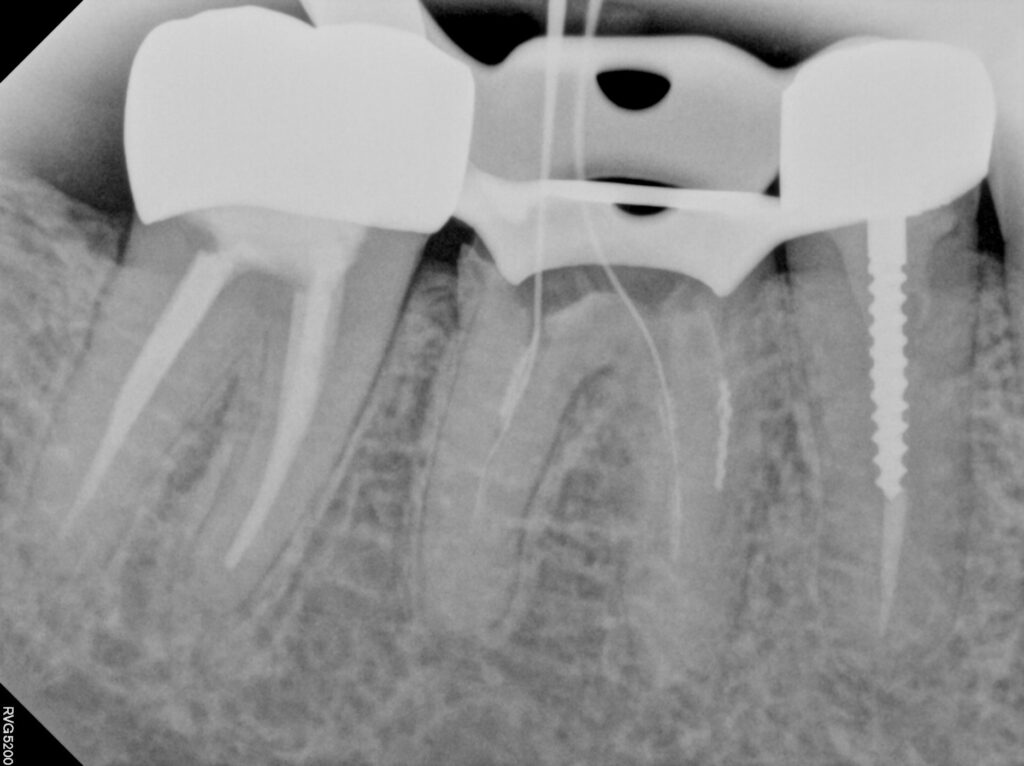

엑스레이 상에서도..

치아 뿌리가 너무 짧고

이차 충치도 있고

심지어 크라운을 만들어 낼 페룰 확보도

어려울 것 같습니다..

오히려 이런경우 치아 뿌리 끝 염증이 없고

더이상 근관을 뚫고 들어가기 어렵기 때문에

이쯤에서 근관 충전을 하기로 합니다

다행히 근관 하나 정도는

길이 확보가 되어서 끝까지 마무리할 수 있었어요

나머지는 되는데까지만 충전합니다

중요한 코어단계인데요

크라운을 유지해줄만한 버팀목이 없기 때문에

포스트를 이용한 레진코어를 만들었어요